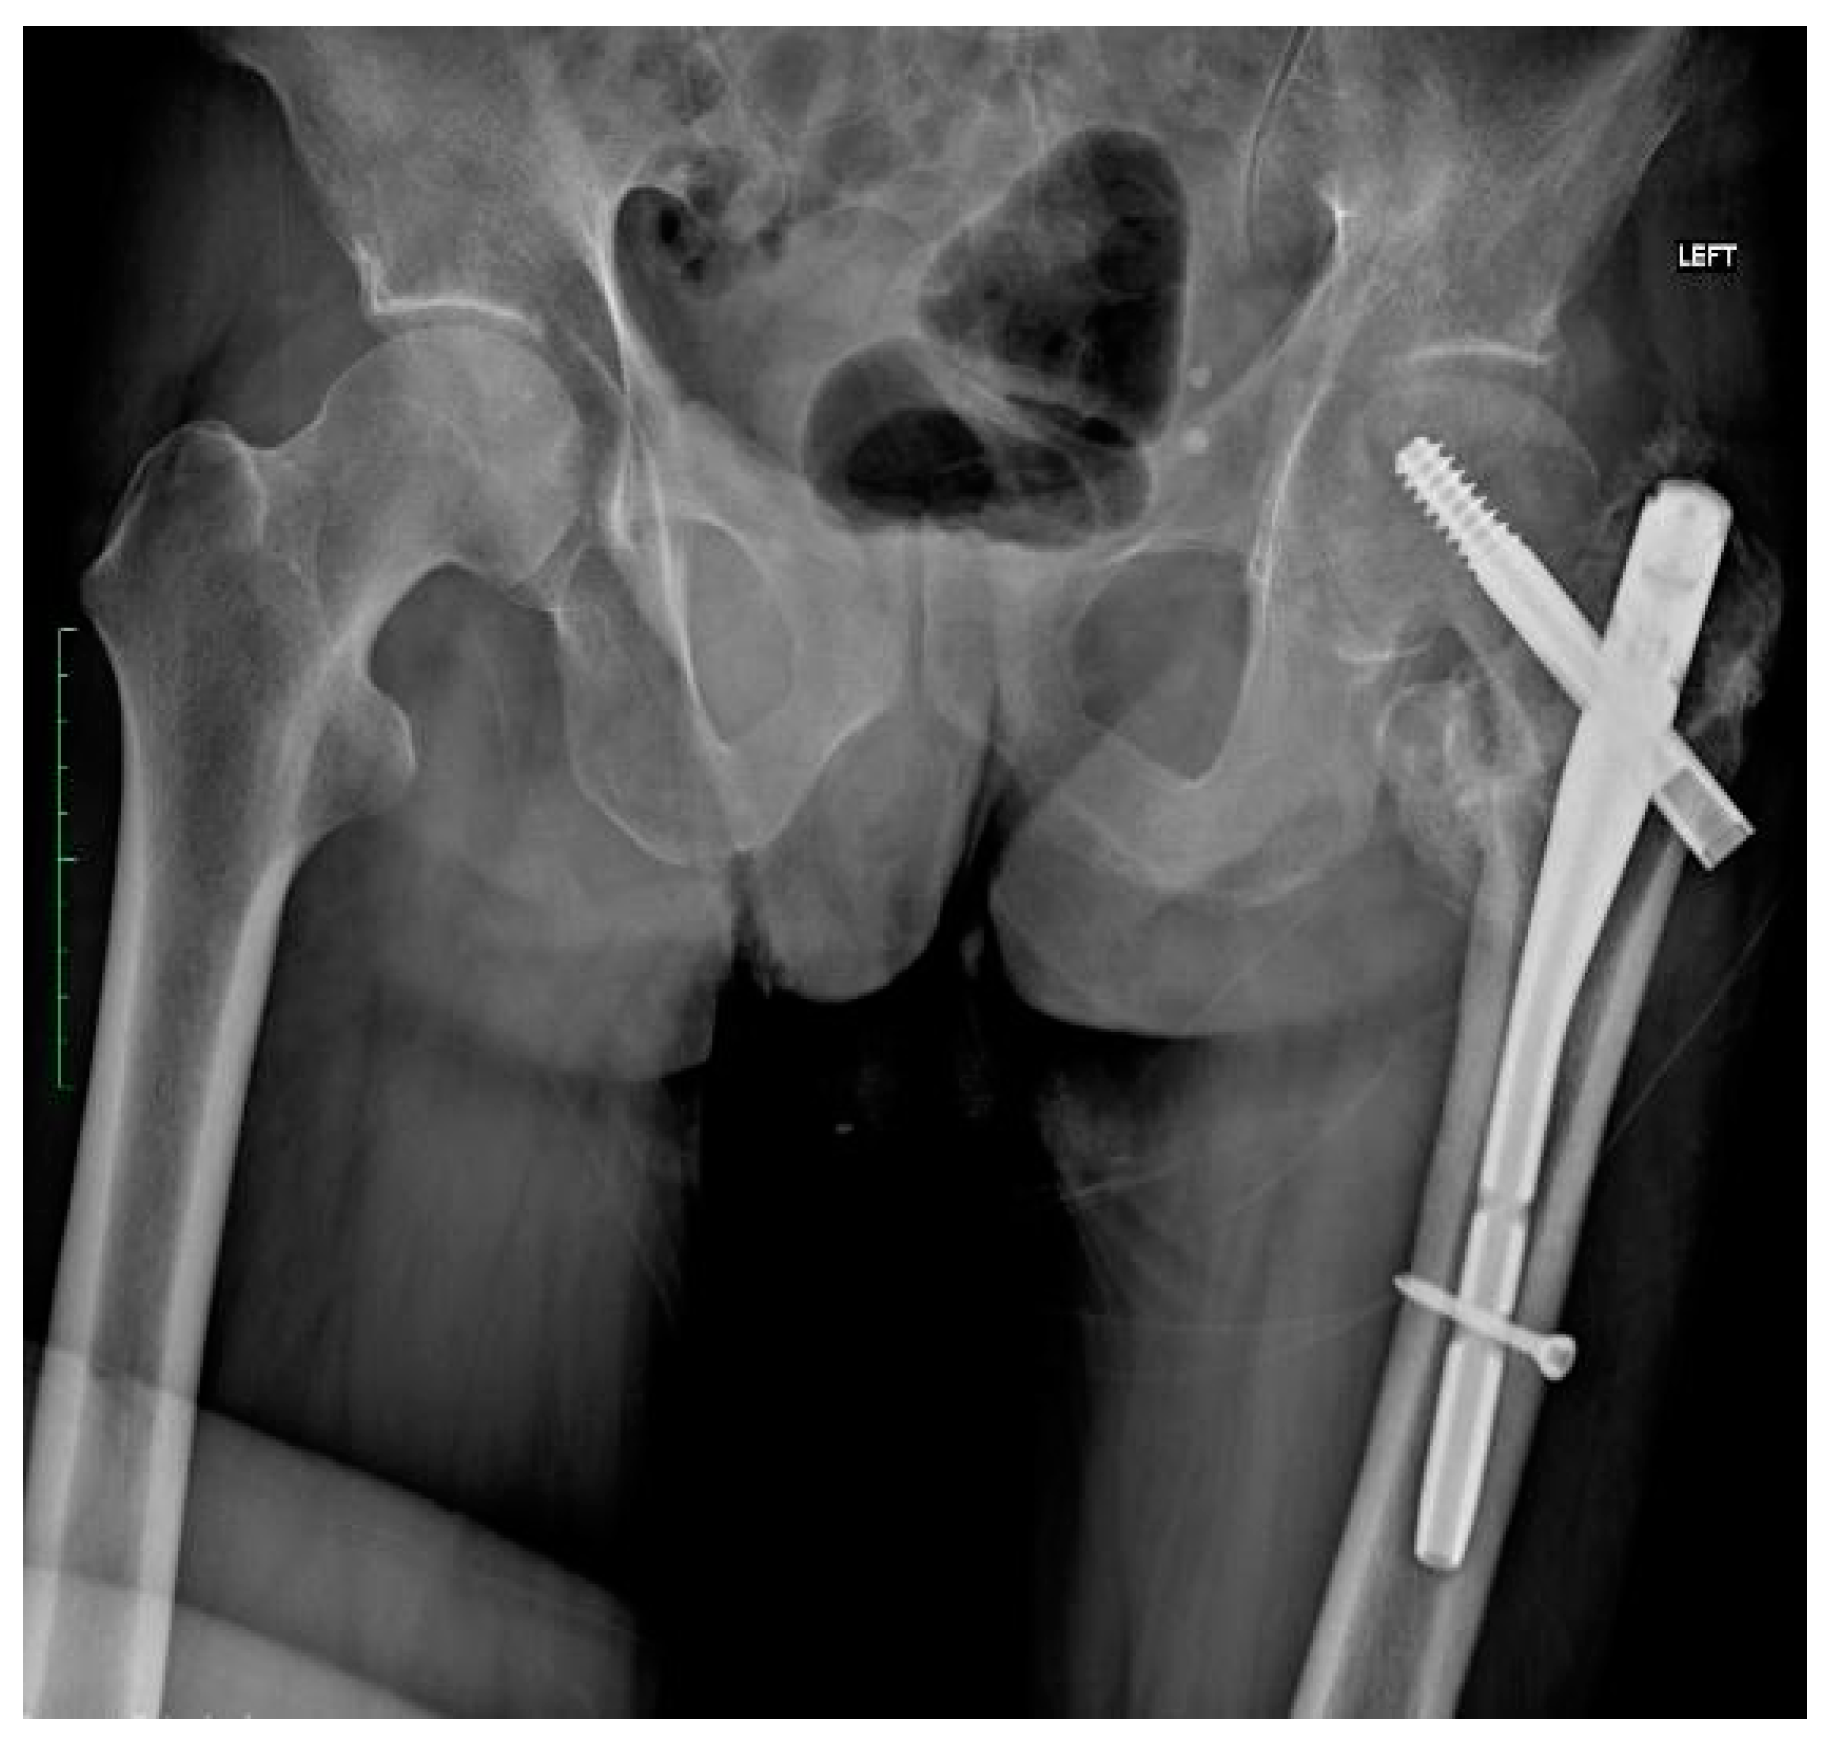

2.4. Fracture and Initial Surgery

2.5. Treatment

| Third Stage of Treatment—October 2023 Snap-on Prosthesoplasty with Adductor Tenotomy | ||